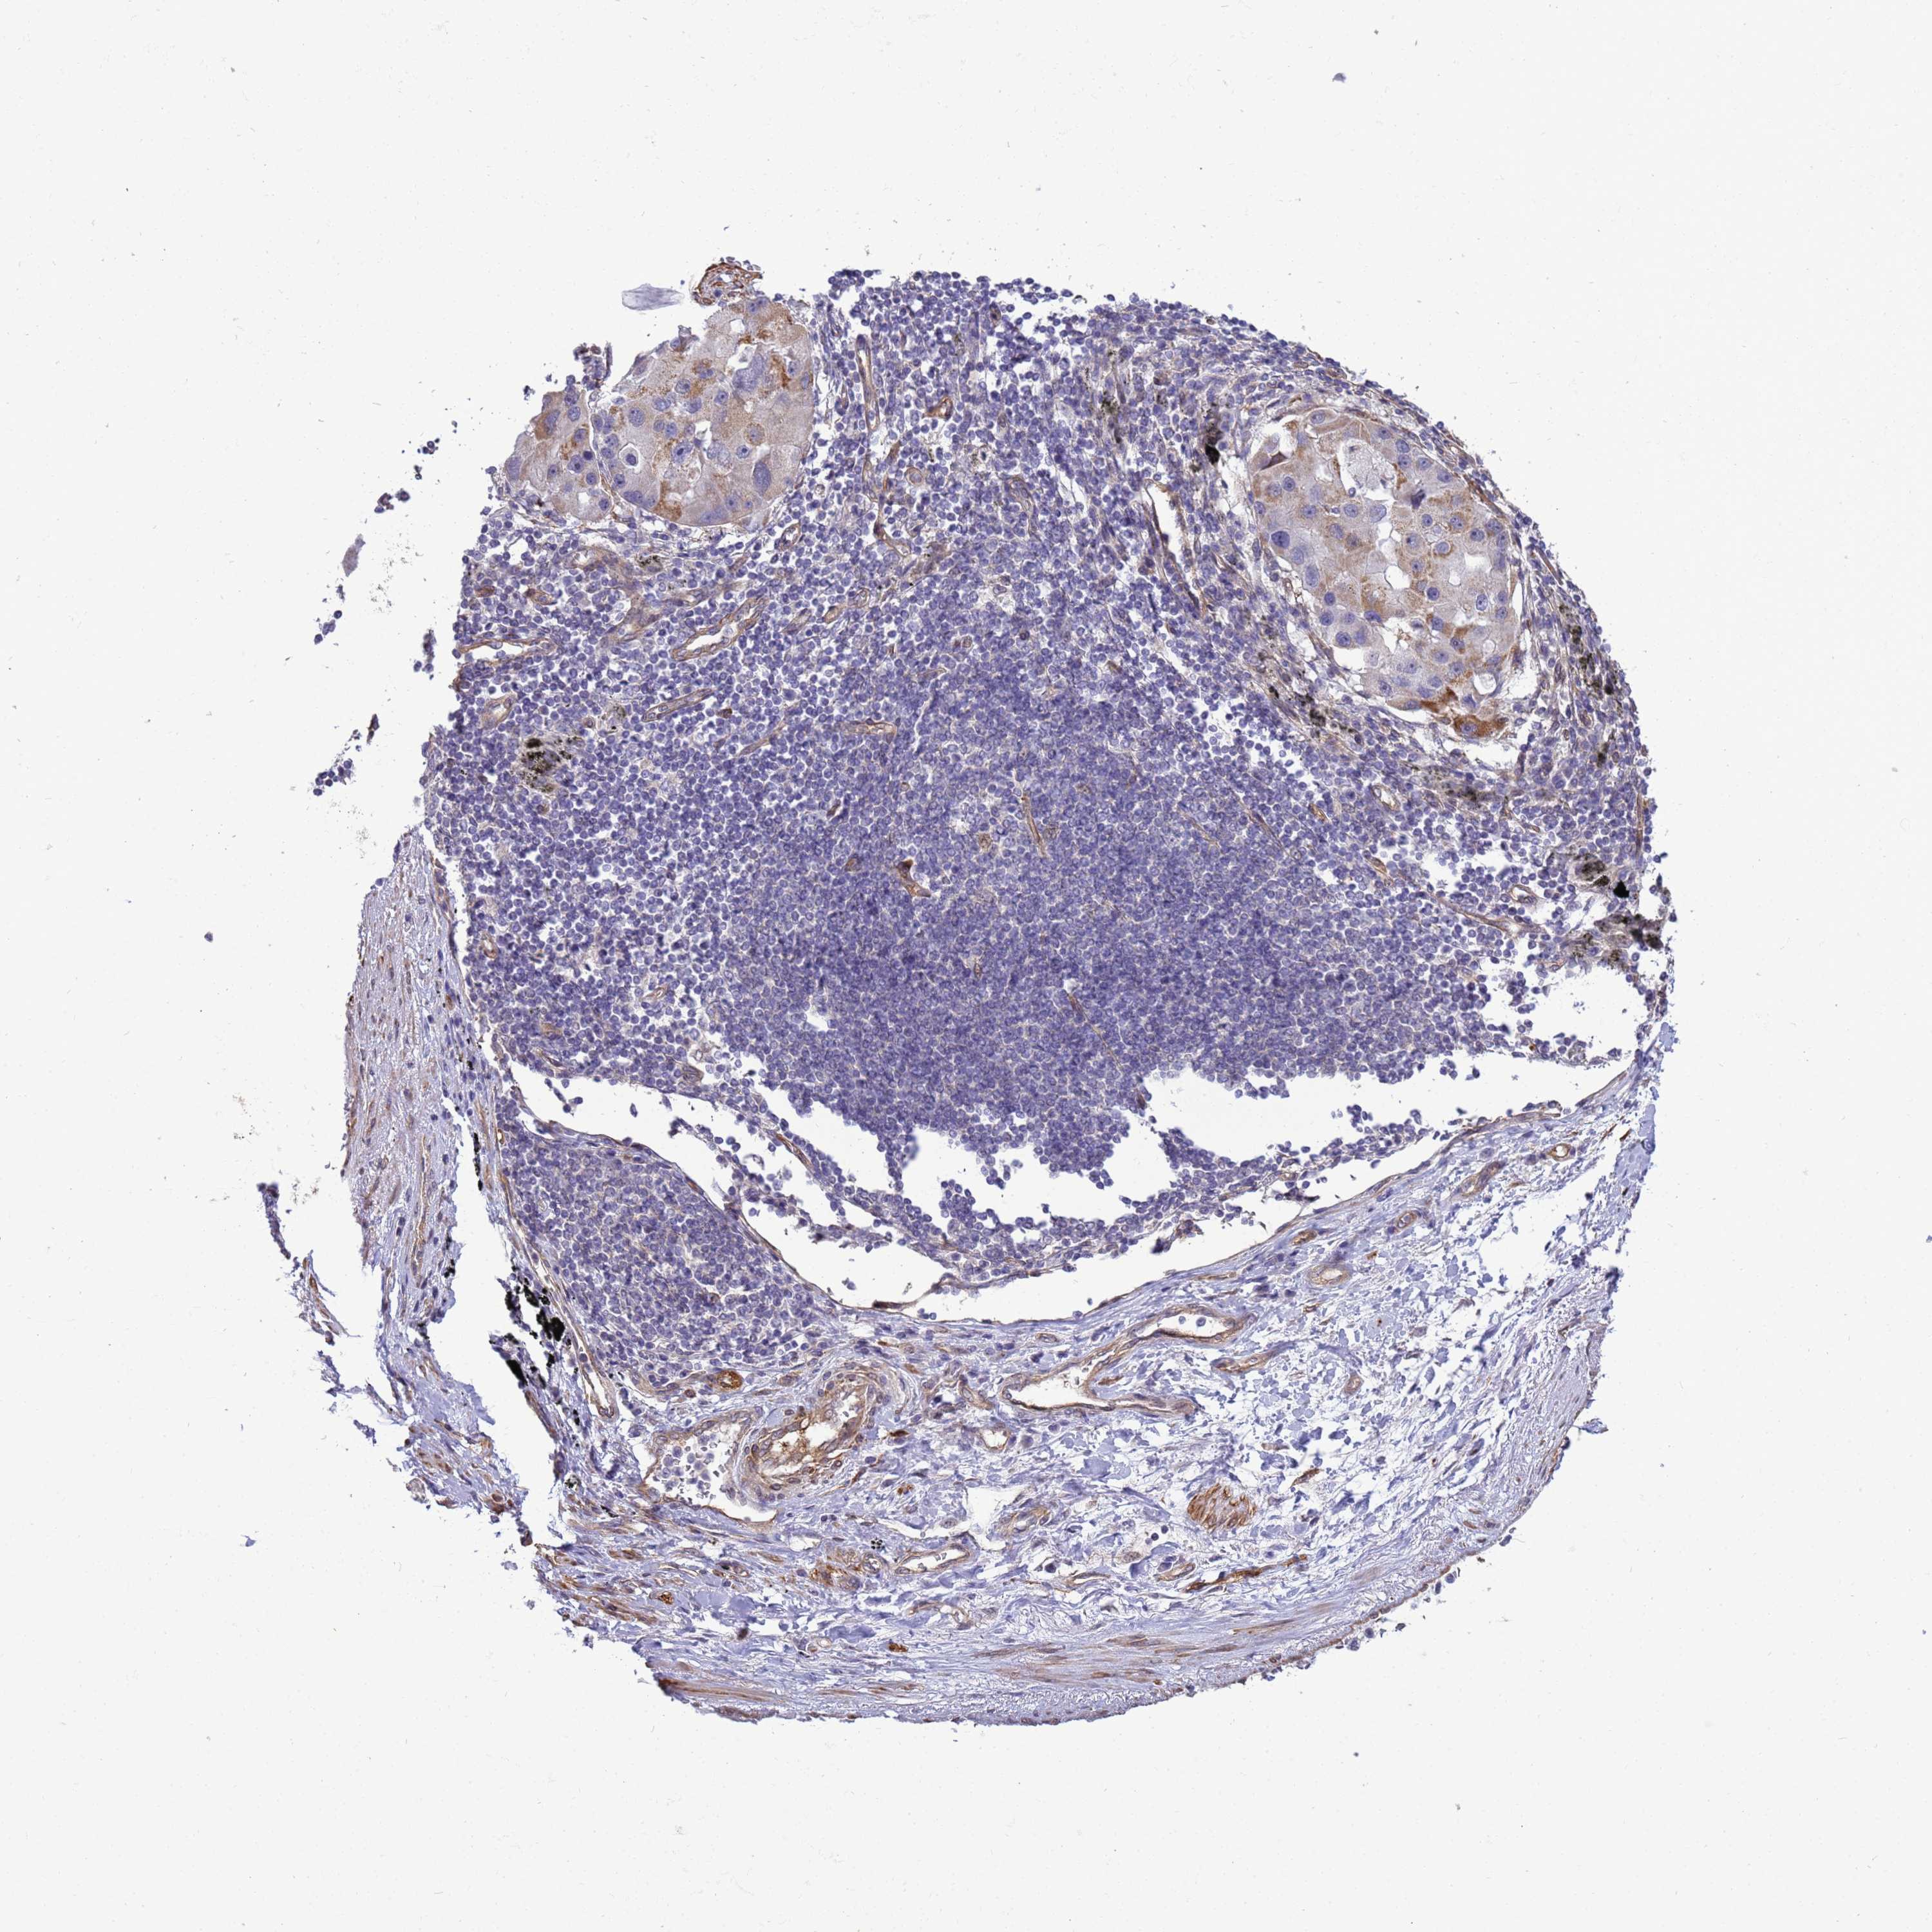

CANCER LUNG CANCER Show tissue menu

ITGB4 is potential prognostic, high expression is unfavorable in Lung Adenocarcinoma (TCGA)